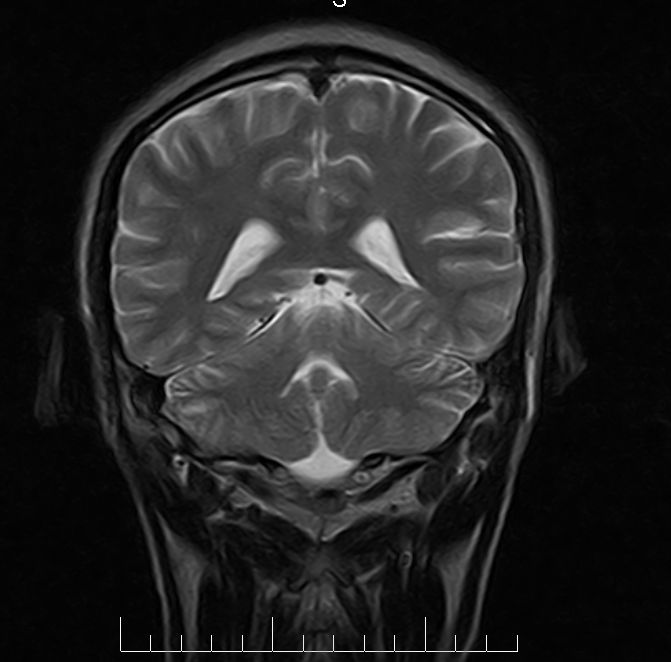

标题: MRI2379:30岁,男,癫痫10年,请各位看一下;CT示:左颞叶钙 [打印本页]

左颞叶区见不规则点状混杂信号影

支持2楼 左颞叶区见不规则点状混杂信号影,考虑动静脉畸形。

考虑左侧颞叶脑血管畸形(avm)。----t1低等高混杂信号,t2等高信号周边较多流空血管影[冠状位明显],mra左侧大脑中动脉受压,远侧聚集.